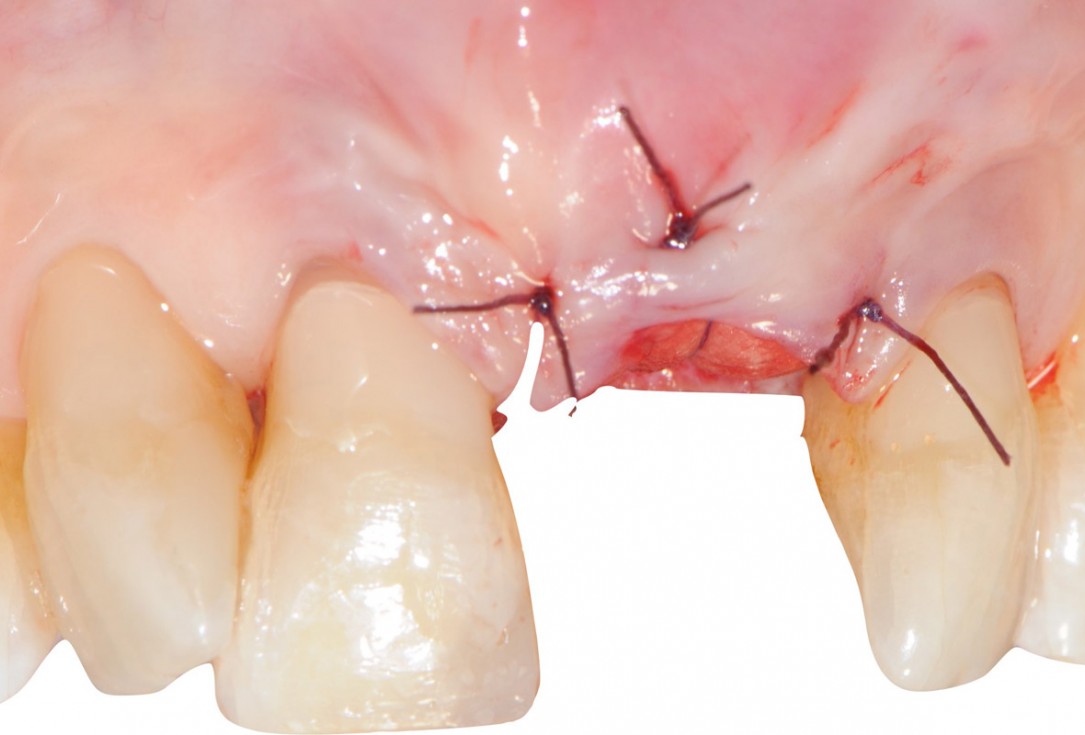

Socket seal with mucoderm® punch